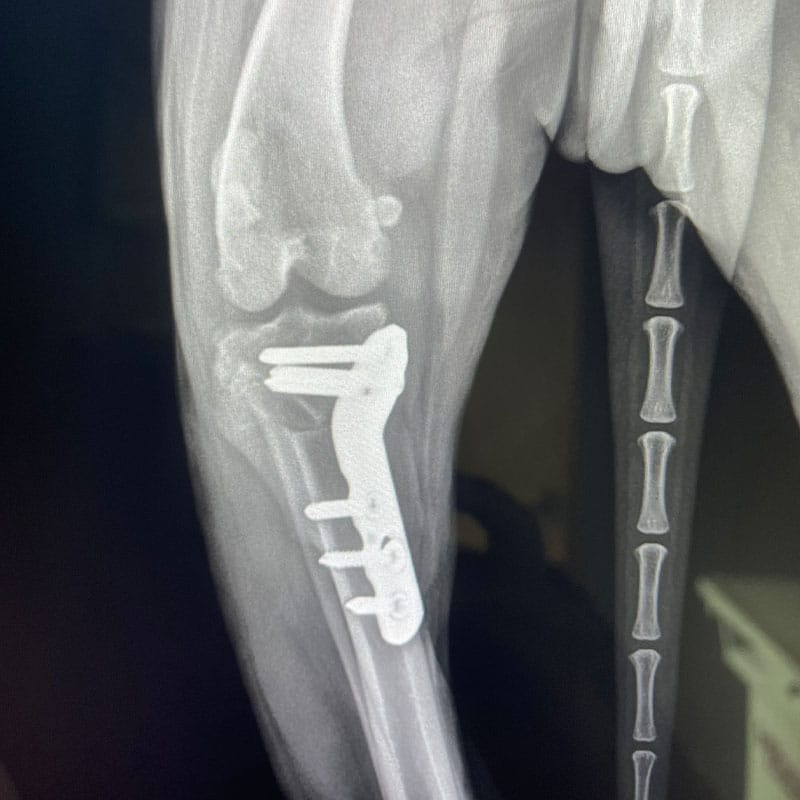

- Orthopedic surgeries (TPLO, fracture repair, luxating patella repair, extracapsular CCL repair, FHO)

- Bone fracture splinting (non-surgical) and some surgical fracture repairs with internal fixation

- Advanced CCL repairs by tibial plateau leveling osteotomy (TPLO) and fracture repairs